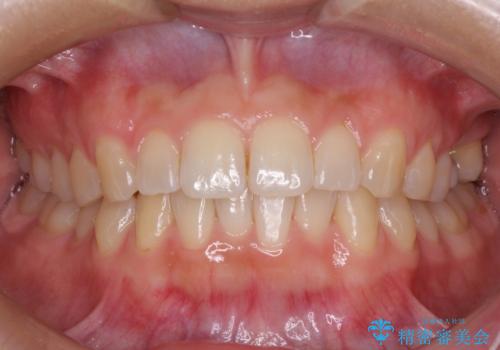

インプラントによる補綴治療とインビザライン矯正

- 抜歯が必要と診断された奥歯を気にして来院された患者様です。

抜歯の上インプラントによる補綴治療を行うこととなりましたが、前歯の叢生も気になるとのことで並行して矯正治療を行うこととしました。

歯列不正は軽微であったので、インビザラインによる矯正治療とし、矯正治療中にインプラント埋入を行う予定としました。

痛みがないので、ボロボロのまま放置していましたが、抜歯後は汚れが溜まりにくくなりスッキリとしたようです。

前歯のデコボコも解消され、ブラッシングが楽になりました。